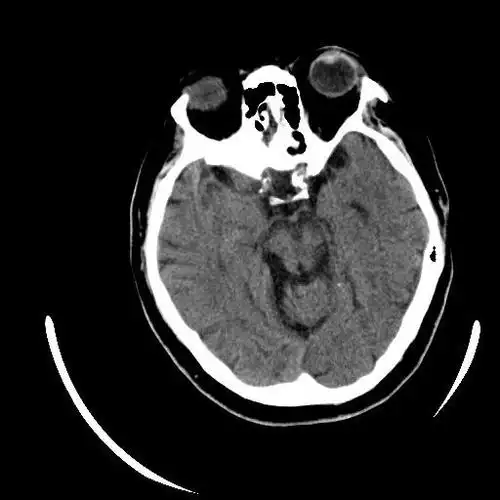

67超急性期大面积脑梗死ct平扫表现